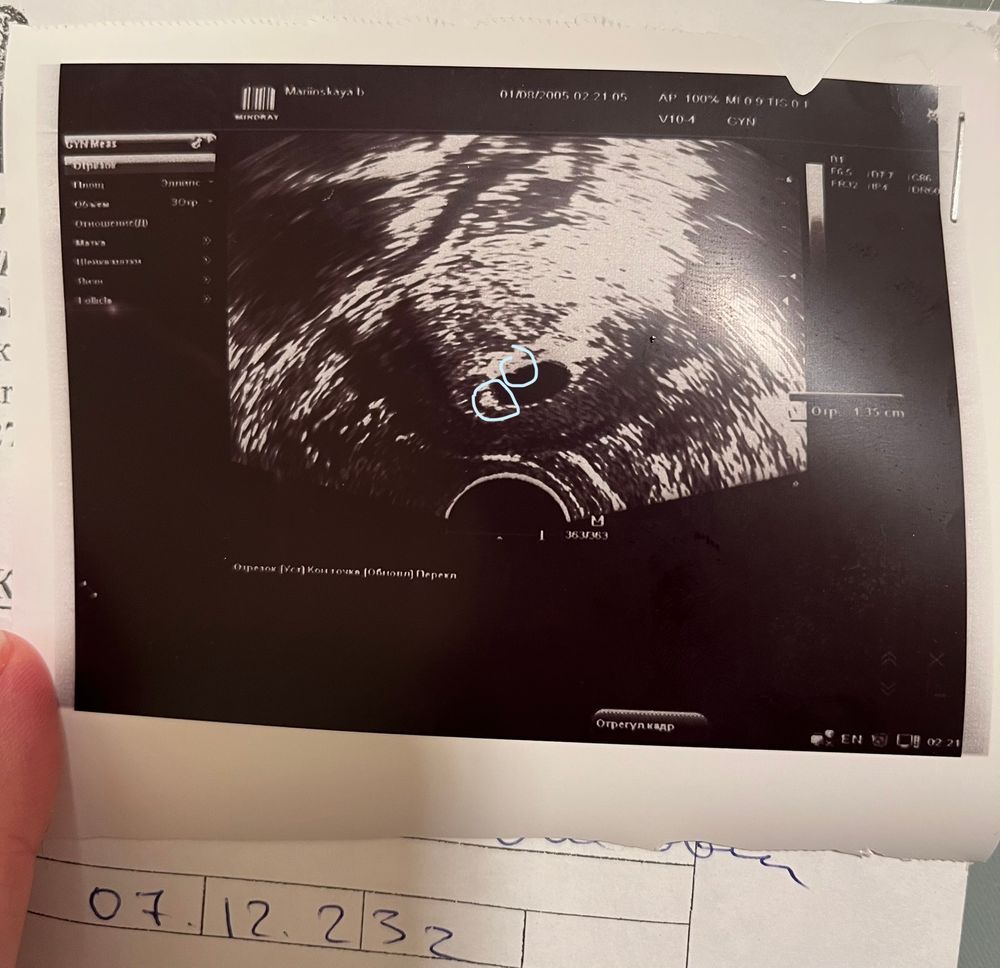

но мне кажется я что-то вижу!!! Поддержку не отменила, буду ждать!!! Записалась завтра на экспертное узи! Посмотрите, видите что-нибудь?

Во первых "срочно" на МА точно не нужно. Если это первое УЗИ, обязательно переделать через неделю (а лучше сейчас проверить у другого узиста и динамику смотреть у него же потом). По фото действительно пусто сейчас. То что вы обвели на фото в комментариях это уже за пределами ПЯ. Но анэмбриония ставится при размерах ПЯ 20-25 мм, так что у вас шансы ещё есть, что все появится, чего вам и желаю 🙌